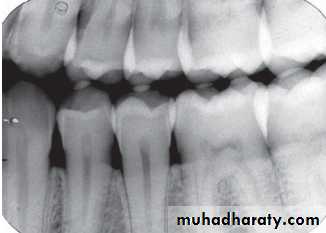

Advantages of the Paralleling Technique

1. Geometrically accurate images are produced with little magnification.2. The shadow of the zygomatic bone appears above the apices of the molar teeth.

3. The periodontal bone levels are well represented.

4. The periapical tissues are accurately shown with minimal foreshortening or elongation.

5. The crowns of the teeth are well shown enabling the detection of proximal caries.

6. The horizontal and vertical angulations of the X-ray tube head are automatically determined by the positioning devices if placed correctly.

7. The X-ray beam is aimed accurately at the centre of the film — all areas of the film are irradiated and there is no cone cutting.

8. Reproducible radiographs are possible at different visits and with different operators.

9. The relative positions of the film packet, teeth and X-ray beam are always maintained, irrespective of the position of the patient’s head. This is useful for some patients with disabilities.